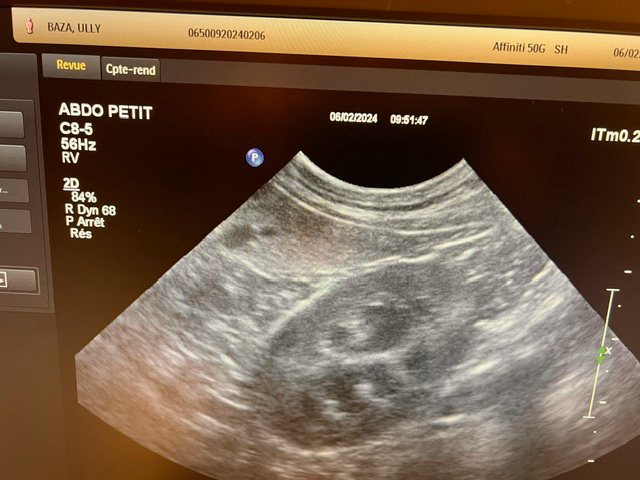

강아지가 목줄을 하고 산책 중에 갑자기 집에 가려고 차도로 뛰어드는바람에 교통사고가 났습니다. 천천히 달려오는 차에 부딪히기는 했지만 걱정돼서 바로 병원으로 갔고 엑스레이, 초음파, 혈액검사 다 시행했지만 이상이 없다고 얘기했습니다. 그런데 사고 이후로 계속 토를 해서 병원에 가서 구토약이랑 진통제를 받아와서 먹였는데도 계속 구토를 하네요ㅠ 사료를 그대로 토하는데 이게 스트레스때문인지 아니면 검사상에 이상이 있는지 여쭤보고 싶어서 글 남깁니다. 또한 가슴쪽을 부딪혔는데 흉부 엑스레이 상에서 이상소견이 있는지 확인 좀 부탁드립니다.

초음파 검사의 경우 초음파를 직접 본 사람이 아니면 찍어놓은 사진으로는 아무런 판단을 할 수 없고 해서도 안됩니다.

주치의의 판단이 가장 정확한 판단이겠으나 지현형으로 장기 손상이 일어나는 경우가 종종 있기 때문에 증상이 지속된다면 복부 초음파 검사를 다시 받아볼 필요가 있어 보입니다.